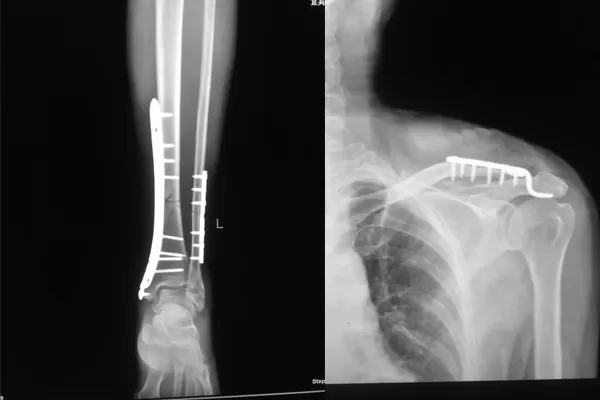

入院不久后,在宜宾民心创伤骨科医院骨科主任的带领下,医疗团队先后为王某成功实施了“左腓骨、左内踝切开复位内固定术+左锁骨切开复位内固定术”

术后一个月,王某已经能丢拐下地行走,目前,王某的伤已经痊愈,近日就可以安然出院了。